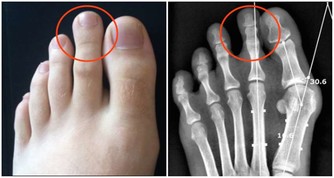

(1)嚴重的肝臟疾病

肝功能受損會導致凝血功能障礙,患者會出現全身各處都有淤青、出血點、破裂後傷口流血不止以及牙齦持續性出血等症狀。

肝臟是合成凝血因子的重要場所。肝供能受損,蛋白質的合成量會減少,相應的,凝血因子的合成量也會減少,這時候身體清除組織凝血活酶和被激活的纖溶因子的能力會下降,出現血液凝固功能障礙。